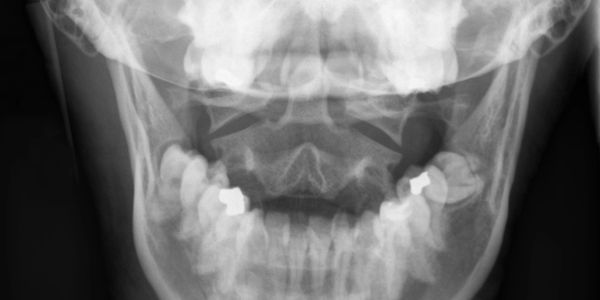

Temporomandibular joint (TMJ) pain

The temporomandibular joint (also known as TMJ) is a complex joint that acts like a sliding hinge, connecting your jawbone to your skull. You have one joint o each side of your jaw.  TMJ pain can cause pain in your jaw joint and in the muscles that control jaw movement.